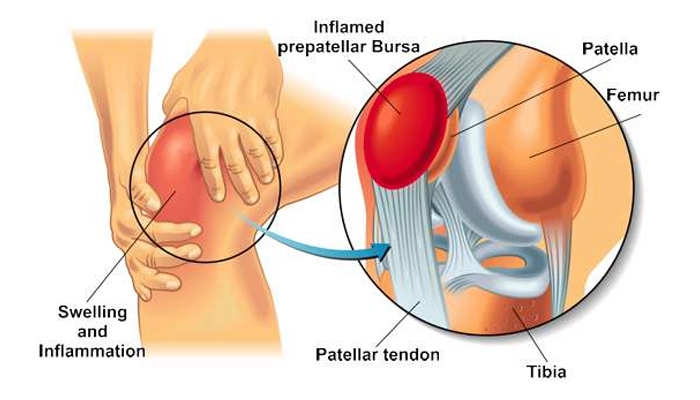

بورسیت پیشکشککی (Prepatellar Bursitis)

در این نوع، التهاب در بورس واقع در جلوی استخوان کشکک اتفاق میافتد. این ناحیه بیشتر در کسانی دیده میشود که زیاد زانو میزنند، مانند نصابها، لولهکشها یا کسانی که در مشاغل سنتی با نشستن روی زمین سر و کار دارند. به همین دلیل به آن «زانوی خانهداری» یا Housemaid’s Knee نیز گفته میشود.

در این حالت، زانو متورم، گرم و حساس میشود. درد معمولاً هنگام فشار دادن زانو یا زانو زدن شدت میگیرد، ولی ممکن است در حرکت ساده احساس کمتری داشته باشد. در موارد شدید، ممکن است مایع زیادی در کیسه جمع شود و حتی عفونت (بورسیت سپتیک) ایجاد کند.

درمان شامل استراحت، استفاده از کمپرس سرد، داروهای ضدالتهاب و در صورت لزوم تخلیه مایع با سوزن یا آنتیبیوتیک برای عفونت است. در بورسیت مزمن مقاوم، تزریق کورتون یا جراحی تخلیه کیسه بورس نیز در نظر گرفته میشود.